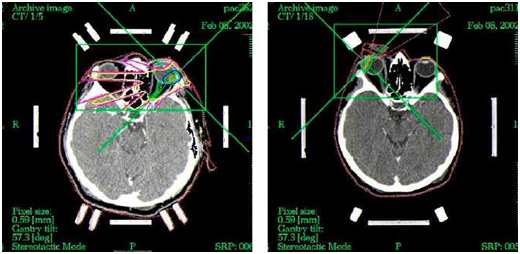

Then the image fusion of CT and MRI contrast is used to calculate the stereotactic treatment planning scheme. The scheme is accordingly optimized against critical structures of the affected eye, such as lens, optic nerve and chiasm (Figure 1). Volume of the tumor influences the calculation of the planned 35.0 Gy therapeutic dose. LSRS is performed on linear accelerator with 6 MeV X. During irradiation at linear accelerator the doses to the critical structures are: less than 8.0 Gy for the optic nerve and the optic disc, and less than 10.0 Gy to the anterior segment of the eye. Just after the LSRS is done the sutures and frame are removed under local anesthesia. Patients after LSRS are followed in three months interval by an ophthalmologist (biomicroscopy, ophthalmoscopy, applanation tonometry, ultrasound, optical coherence tomography) and in six month interval are screened by MRI of the orbit plus metastasis screening (liver ultrasound, liver function test; chest X-ray).

Figure 1 Two examples of computer images with calculated and optimized LSRS dose planning scheme for malignant uveal melanoma treatment.